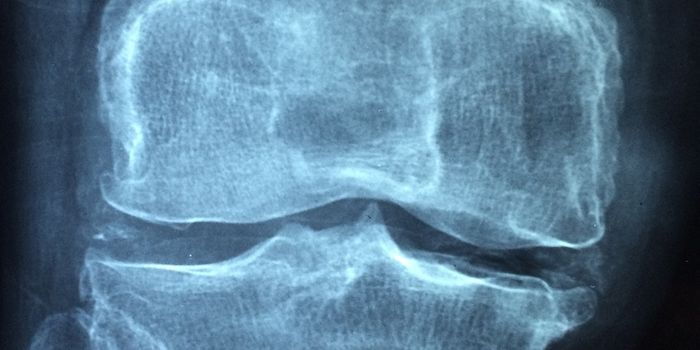

JAN 29, 2024Drug Discovery & DevelopmentOsteoporosis, a condition characterized by reduced bone density and an increased risk of fractures, is linked to systemi ...

NOV 16, 2023NeuroscienceCannabidiol (CBD) and cannabigerol (CBG) may offer potential pain management for bone fracture patients. A Penn State Un ...